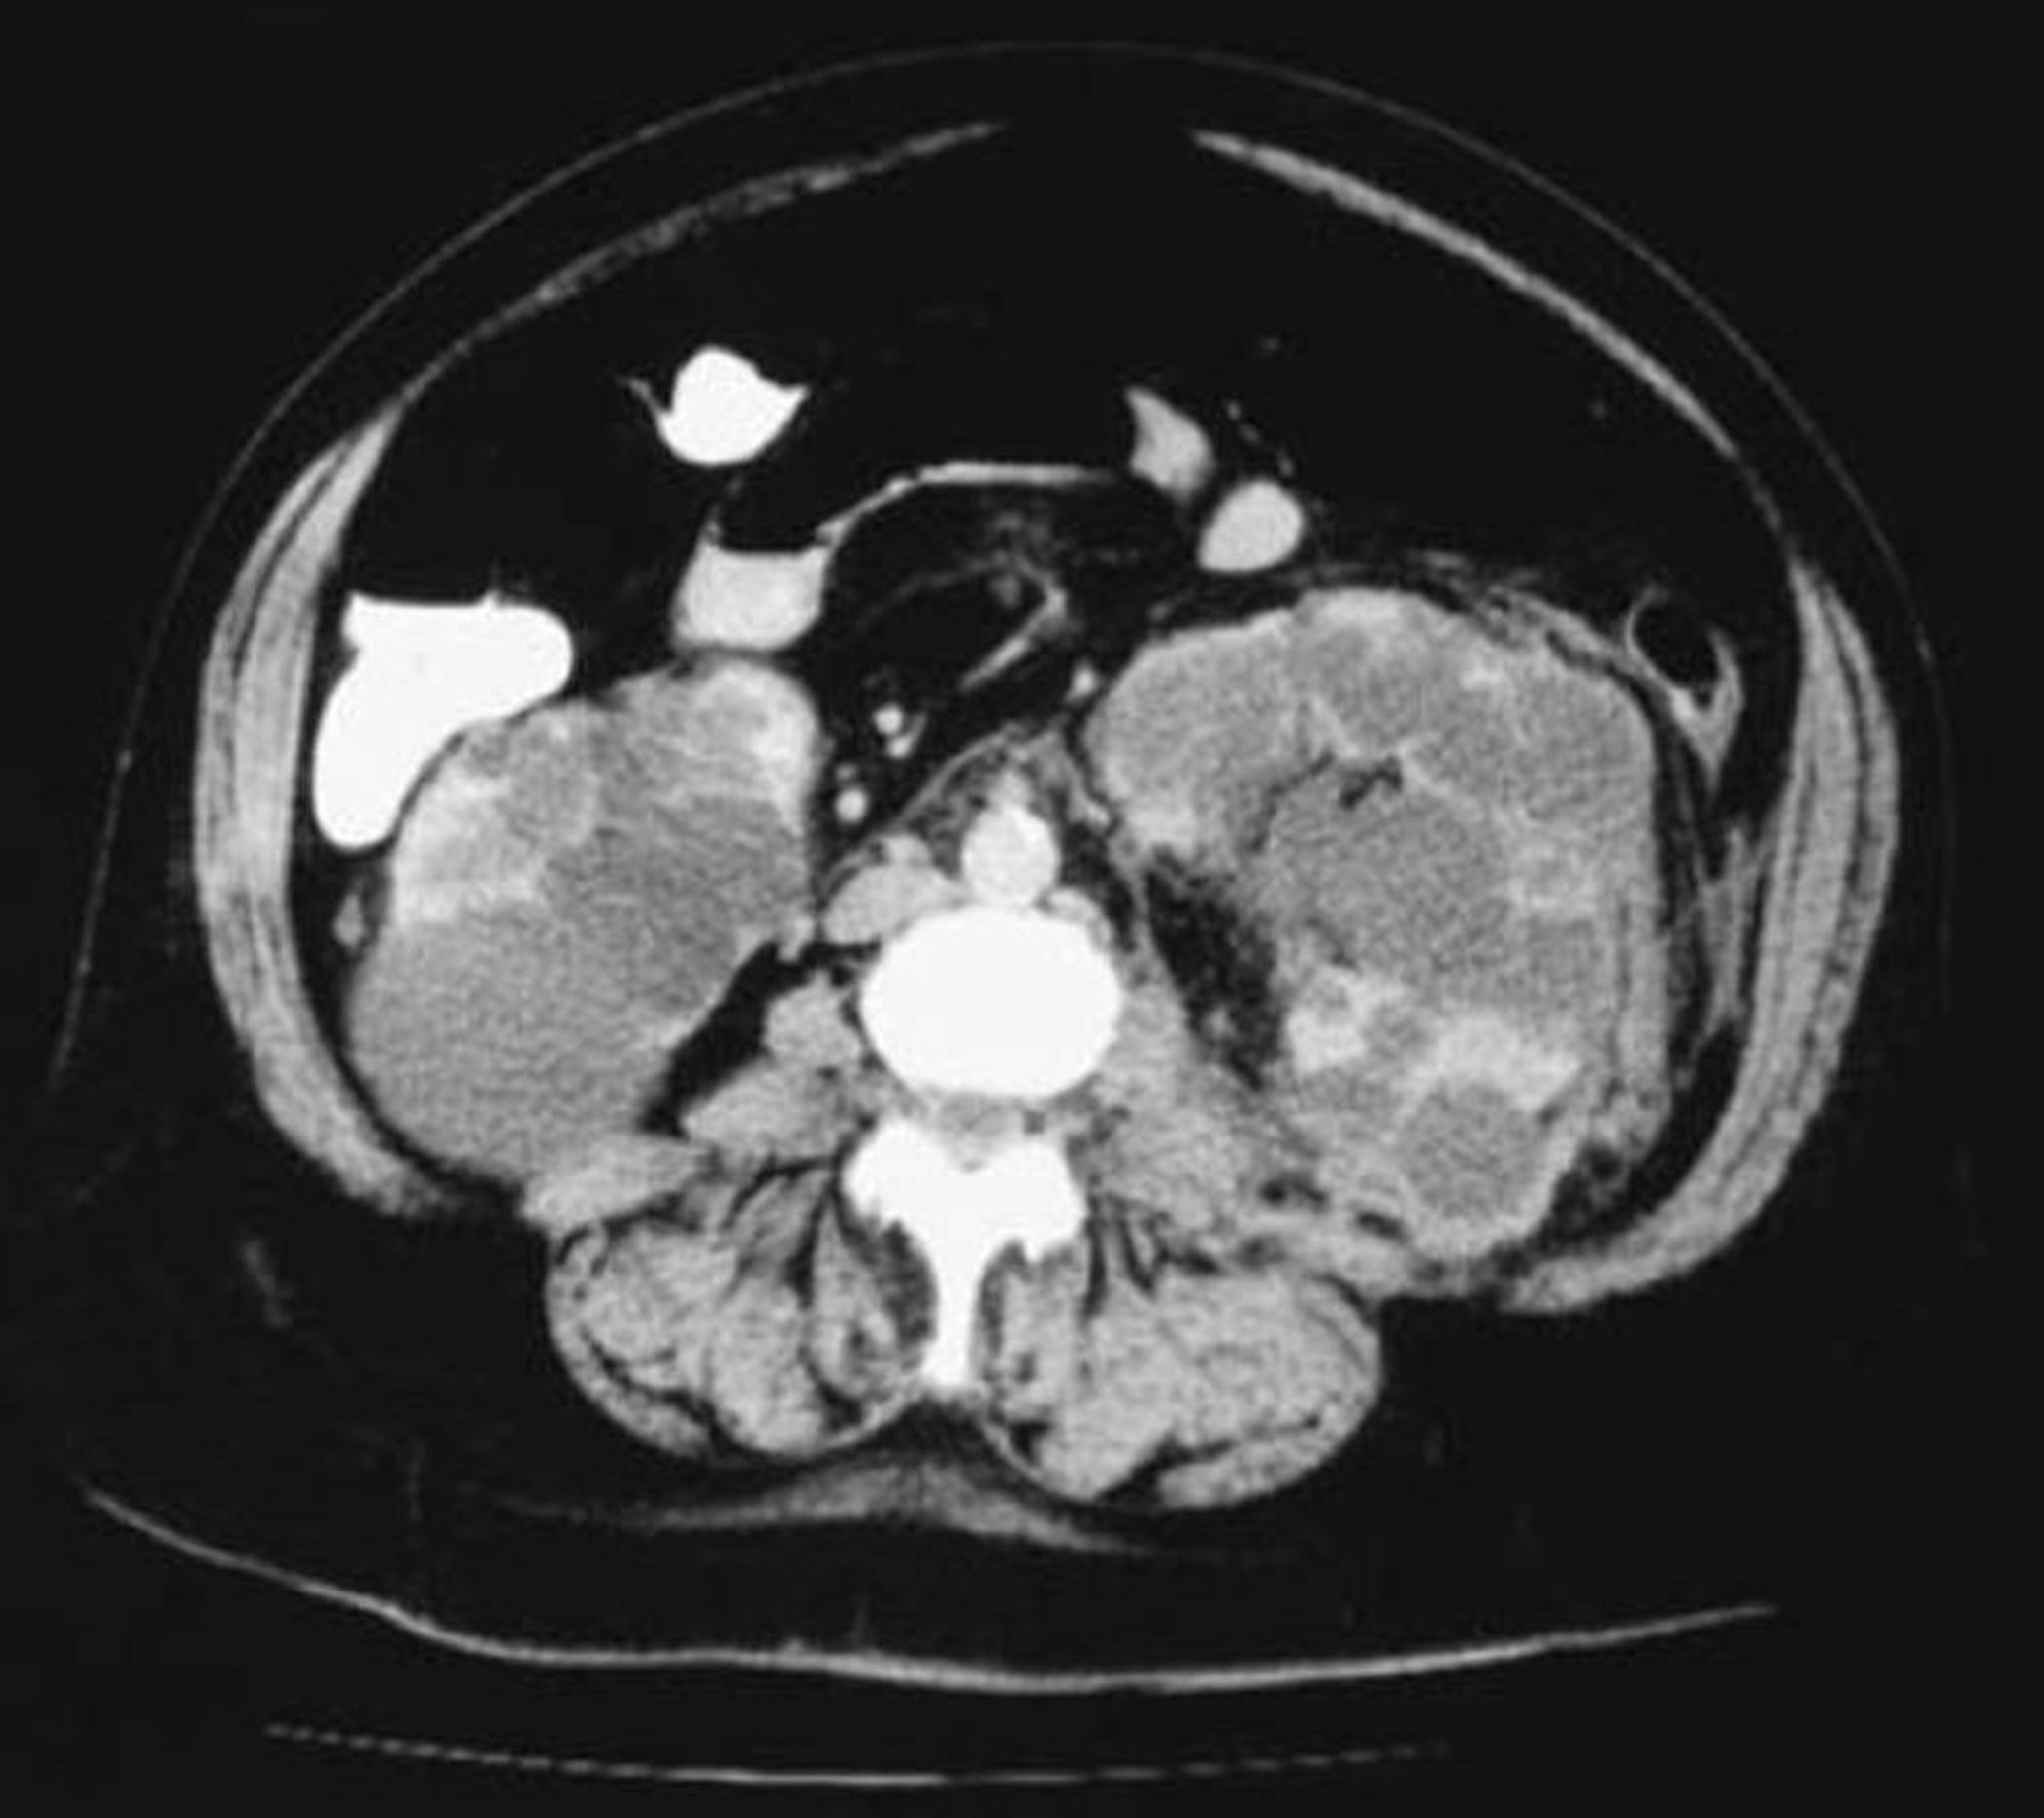

Incidência axial na TC de rins policísticos

Essa TC dos rins mostra inúmeros cistos variando em tamanho. Pouco parênquima renal permanece.